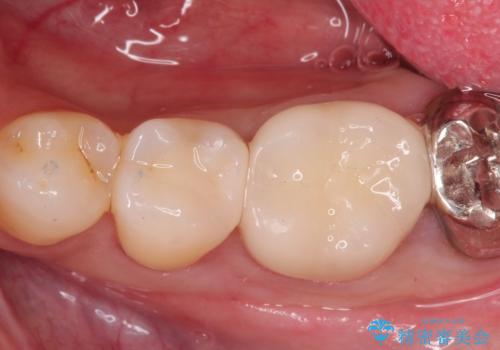

[ セラミック治療 ]目立つ奥歯の銀歯を白くする

![[ セラミック治療 ]目立つ奥歯の銀歯を白くするの症例 治療後](https://seimitsushinbi.jp/wp/wp-content/uploads/2021/11/2d1e50d0178f2ec9668274932161b9f7-500x350.jpg?v=1637229912)